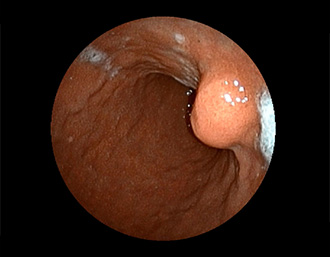

症例5:胃腺腫(84才女性)

胃角部に、大きさ10mm強のなだらかな粘膜隆起を認める。生検:Tubularadenoma with moderate atypia.Group 3。経過観察中。

(通常画像)